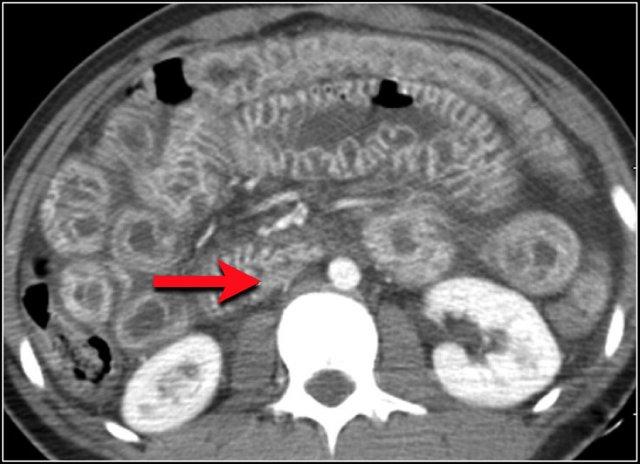

Các hình ảnh này thuộc về bệnh nhân bị tắc ruột non dạng quai kín.

Lưu ý nhóm các quai ruột non có thành dày ở vùng bụng trên phải (mũi tên vàng).

Phù nề mạc treo ruột (mũi tên đỏ) cho thấy tình trạng tăng áp lực tĩnh mạch do thắt nghẹt.

Giãn mạch máu

Tăng áp lực tĩnh mạch trong thắt nghẹt cũng dẫn đến giãn tĩnh mạch (mũi tên vàng).

Bệnh nhân này cũng có tắc ruột dạng quai kín với kiểu ngấm thuốc xám của các quai ruột bị thắt nghẹt (mũi tên đỏ).

Lưu ý sự ngấm thuốc bình thường của ruột non ở phía trên vị trí tắc nghẽn (mũi tên xanh lá).